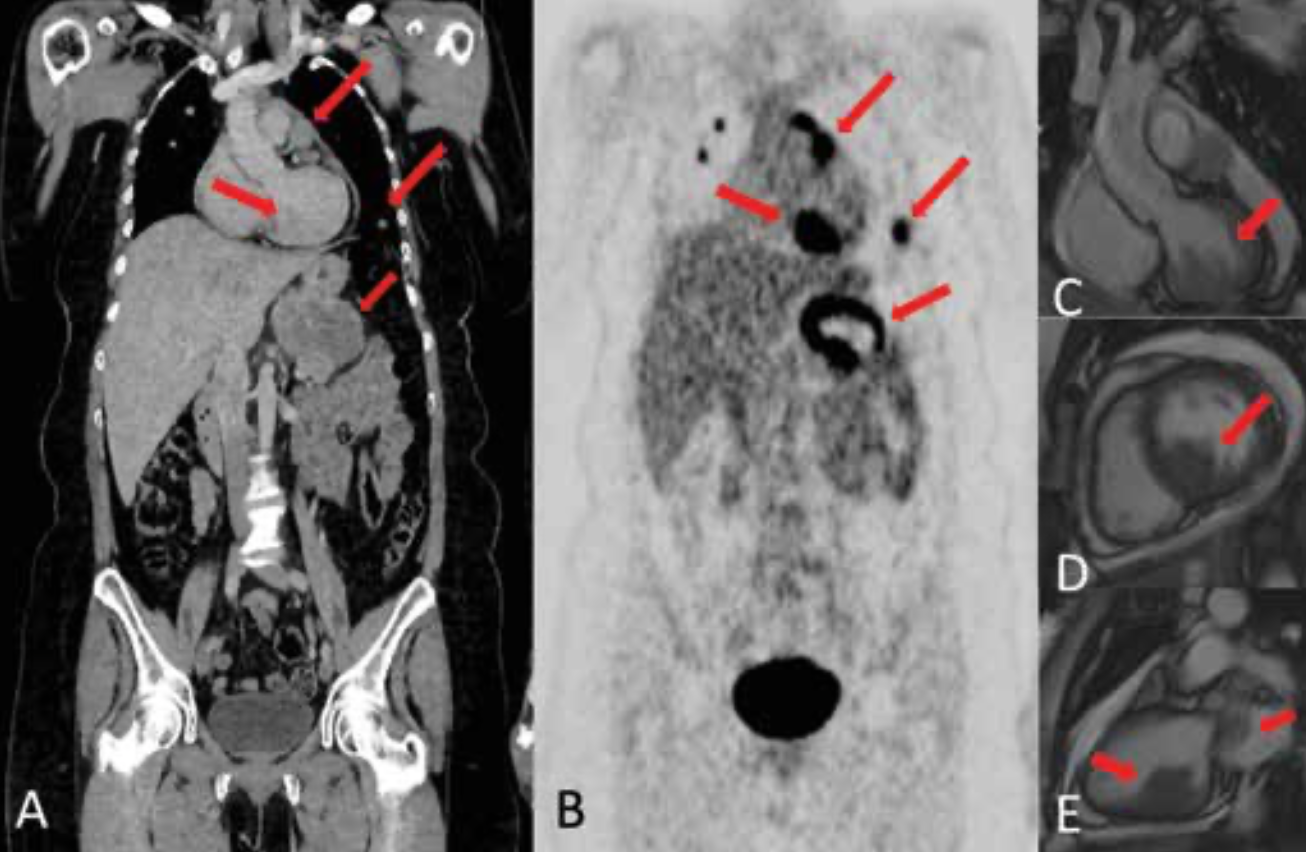

In 2017, multiple lung and pancreatic metastases were detected in a follow-up PET scan. A brain MRI was performed; no evidence of disease was found. A BRAF V600E mutation was documented. Treatment with nivolumab (Opdivo) was started. After 9 months of treatment, progression of disease to soft tissue, myocardium, pericardium, lung, pancreas, left adrenal gland, and bone was documented (Figure 1). Treatment with dabrafenib (Tafinlar) plus trametinib (Mekinist; D+T) was started. A reduction of the tumor burden was achieved after 2 months of treatment, and after 6 months, the patient had a deep partial response of more than 80% reduction of the tumor load. After 1 year of treatment, the patient came to the clinic with neurological symptoms. A brain CT scan revealed multiple supratentorial lesions, with the largest, measuring 23 mm, localized in the parietooccipital region. Other lesions, each measuring less than 1 cm, were localized in the right parietal region, frontal region, and left parietal lobe (Figure 2A). A CT scan ruled out progressive disease in other sites (Figure 2B).

FIGURE 1. PET-CT scan (A, B) reveals metastatic disease in mediastinum, myocardium, lung,

and pancreas. Cardiac MRI shows a lesion

(C, D, E) in the left ventricle infiltrating the papillary muscles and the ventricular wall. Intravascular lesion in the pulmonary artery is present, with outflow obstruction.